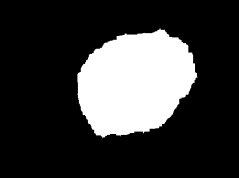

Skin lesion segmentation is one of the crucial steps for an efficient non-invasive computer-aided early diagnosis of melanoma. This paper investigates how color information, besides saliency, can be used to determine the pigmented lesion region automatically. Unlike most existing segmentation methods using only the saliency in order to discriminate against the skin lesion from the surrounding regions, we propose a novel method employing a binarization process coupled with new perceptual criteria, inspired by the human visual perception, related to the properties of saliency and color of the input image data distribution. As a means of refining the accuracy of the proposed method, the segmentation step is preceded by a pre-processing aimed at reducing the computation burden, removing artifacts, and improving contrast. We have assessed the method on two public databases, including 1497 dermoscopic images. We have also compared its performance with classical and recent saliency-based methods designed explicitly for dermoscopic images. The qualitative and quantitative evaluation indicates that the proposed method is promising since it produces an accurate skin lesion segmentation and performs satisfactorily compared to other existing saliency-based segmentation methods.